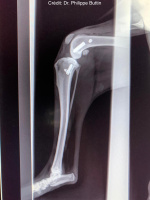

Radiologické snímky